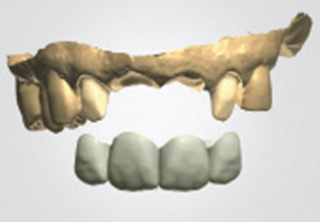

흔히 "네비게이션 임플란트"라고 말하는 컴퓨터 분석을 이용한 임플란트란?

컴퓨터 분석을 이용한 임플란트는 3차원 영상 분석을 통하여 적절한

임플란트의 식립 위치와 방향 등을 결정하여 치료계획을 수립하고,

이를 토대로 개별 맞춤 수술유도장치를 제작하여 시술하는 방법입니다.

일반적으로 잇몸을 절개하지 않고 시술하여 수술시간이 짧으며, 수술 후 통증이나 붓기, 출혈이 적은 장점이 있습니다.

3D 모의시술로 식립

시술 전 3D영상장치 등을 통한 진단계획과

모의 수술을 통해 환자의 골조직과 신경관의

위치 등을 파악하여 명확한 치료 계획을

수립하고 개별 맞춤 수술유도장치를

사용하므로 신경 손상 및 부정확한 임플란트

시술의 위험이 적습니다.